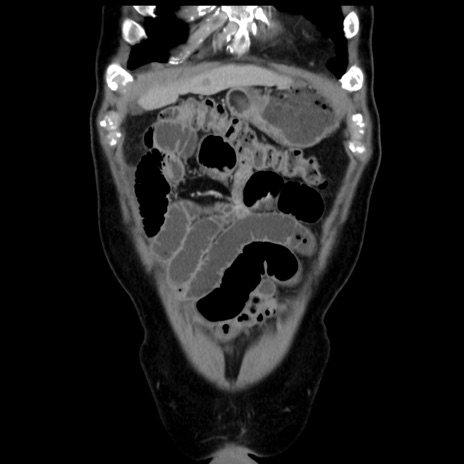

症例16(冠状断像)

【症例】 70歳代男性

【主訴】 腹痛、嘔吐

【現病歴】 約1ヶ月前より間欠的に腹痛と嘔吐あり、当院消化器内科を受診したところCTで多発する肝臓のLDAを指摘され、精査中であった。以降は消化器症状は安定していたが、2日前より嘔気と腹痛があり、同日より排便・排ガスが消失した。改善認めず、 本日、救急外来を受診した。

【既往歴】 大腸ポリープ切除後。

【身体所見】意識清明・会話良好、BT 36.3℃、BP 127/80mmHg、 P 80bpm、腹部:膨満あり、平坦・軟、上腹部正中および下腹部正中に圧痛あり、反跳痛なし、筋性防御なし。

【データ】WBC 7200、CRP 0.77